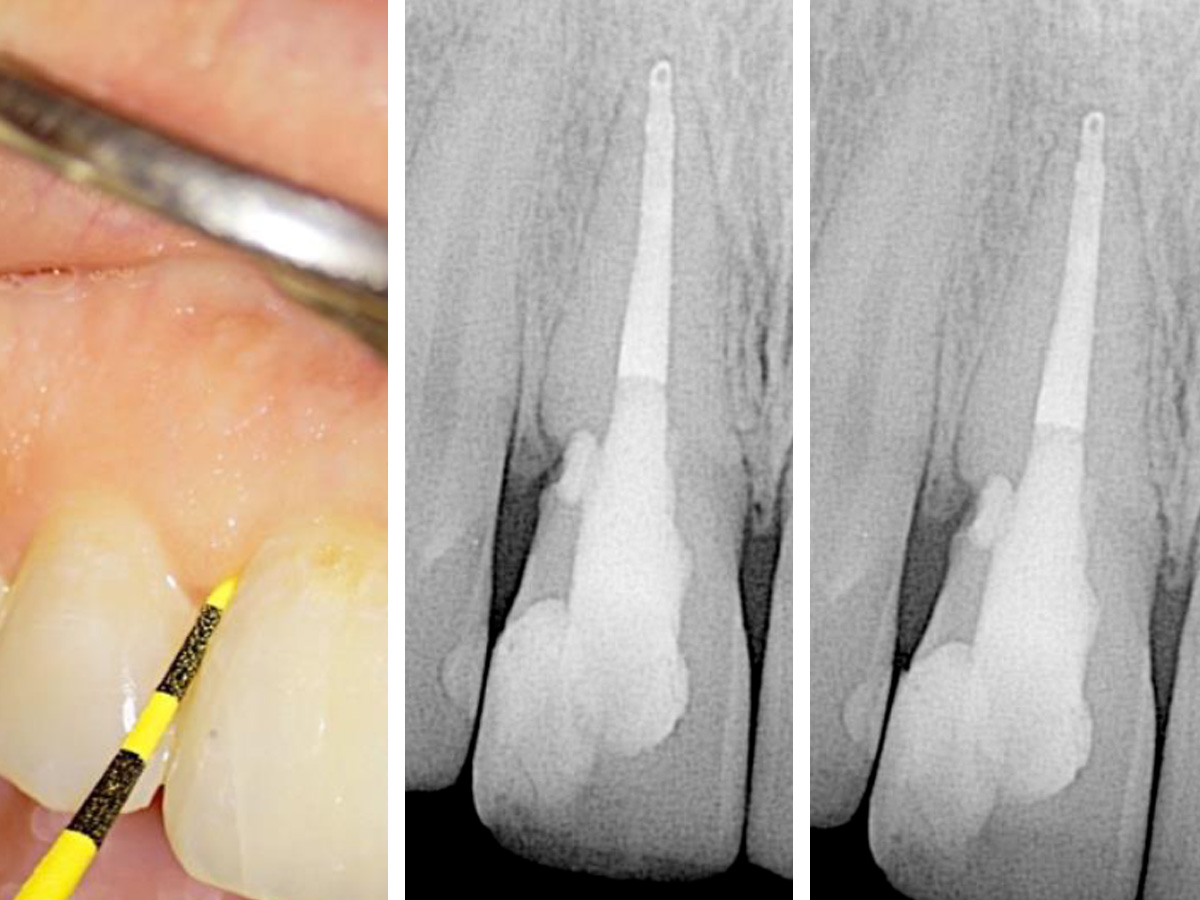

Abbildung 2

Zu sehen ist der blutende Defekt im zervikalen Bereich zu Beginn der Wiedereröffnung des Wurzelkanals.

Zu Beginn der Behandlung wurde zunächst so viel vom Gutta-Percha wie nur möglich entfernt und der Wurzelkanal anschließend desinfiziert. Man konnte eine Blutung des resorptiven Defekts erkennen. Der Kanal und der Defekt wurden mit Kalziumhydroxid gefüllt und der Zugang mit IRM versiegelt (Abb. 2).

Nach zwei Wochen stellte sich die Patientin symptomfrei vor. Die Fistelöffnung war verschwunden und der resorptive Defekt blutete nicht mehr. Die Behandlung wurde fortgesetzt und erneut wurde Kalziumhydroxid in den Wurzelkanal gefüllt. Da der resorptive Defekt trocken und zugänglich war,wurde entschieden den resorptiven Defekt mit BC Putty durch die Zahneröffnung (internes Vorgehen) zu füllen (Abb. 3).